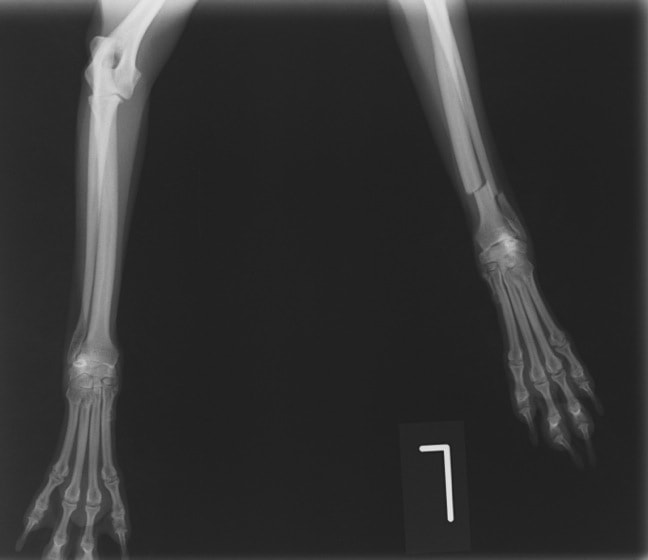

橈尺骨骨折 : 症例1 | 症例2 | 症例3 | 症例4 | 症例5 | 症例6 | 症例7

: 症例8 | 症例9 | 症例10 | 症例11 | 症例12 | 症例13 | 症例14

: 症例15 | 症例16 | 症例17 | 症例18 | 症例19 | 症例20 | 症例21